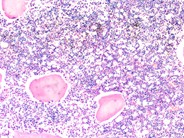

Niemann-Pick diseases - Humpath.com - Human pathology from www.humpath.com For people with mild to moderate type c, a drug called miglustat (zavesca) may be an option. This is a group of disorders. It breaks down a fatty. Esto significa que ambos padres son portadores. In types a and b, people lack an enzyme called acid sphingomyelinase (asm). Aug 23, 2016 · metabolism is the process your body uses to make energy from the food you eat. These cells malfunction and, over time, die. Cada uno de los padres tiene 1 copia del gen anormal sin manifestar ningún signo de la enfermedad.

Source: imagebank.hematology.org It belongs to a family known as lysosomal storage diseases and is caused by. Chemicals in your digestive system (enzymes) break the food parts down into sugars and acids, your body's fuel. Elle aboutit à l'accumulation de sphingomyéline , puis de cholestérol dans les monocytes , voire dans le cerveau (type a). No effective treatment is available to people with type a or b. Jun 18, 2021 · the u.s.

Source: imagebank.hematology.org Cada uno de los padres tiene 1 copia del gen anormal sin manifestar ningún signo de la enfermedad. In types a and b, people lack an enzyme called acid sphingomyelinase (asm). It breaks down a fatty. No effective treatment is available to people with type a or b. Orphazyme a/s company announcement no.